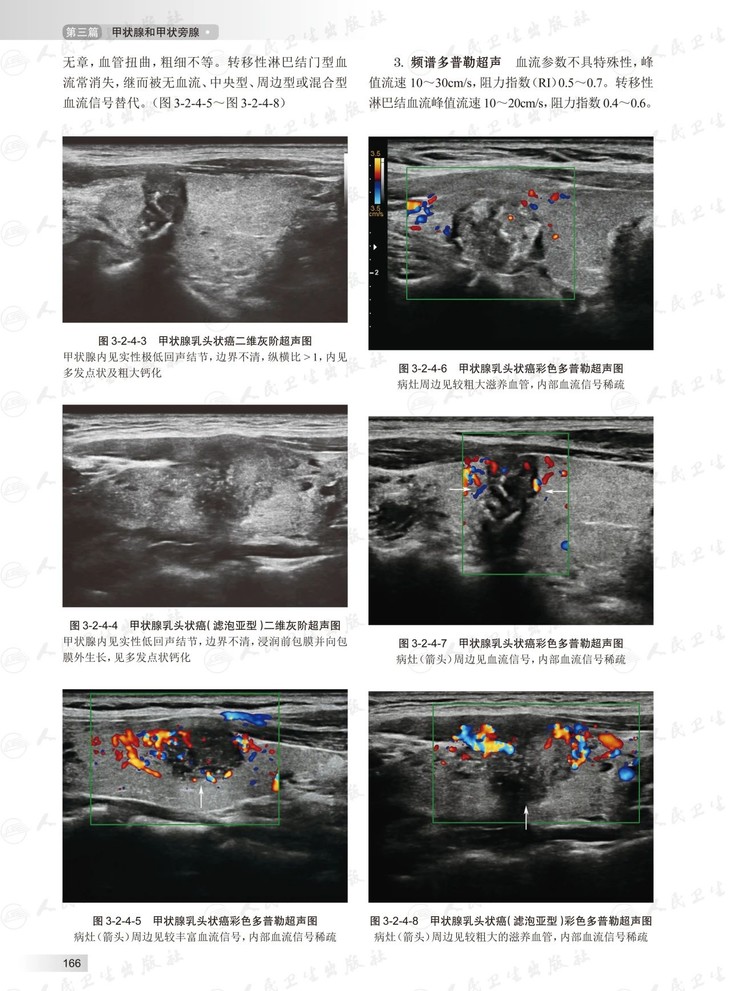

本书将系统介绍甲状腺、乳腺、涎腺、男性生殖器、软组织包块(皮肤、其他部位淋巴结)、颅内血管及外周血管等的超声诊断标准、诊断与鉴别诊断,还将加入超声新技术、介入诊断及治疗等会分别进行论述。力争全面、系统、详实、实用,体现国内超声医学专家在当下对学科的认识水平,涵盖超声诊疗领域的新进展、新技术、新知识,并着重拓宽研究生临床思维、增强科研意识、提高其科研水平。力争成为不同层次超声医师的日常参考书、诊断智库。同时,本书还将充分利用互联网载体的优势,与纸书同步推出“中华浅表器官超声病例库”,最大限度的展现超声医学“靠图说话”的特点。